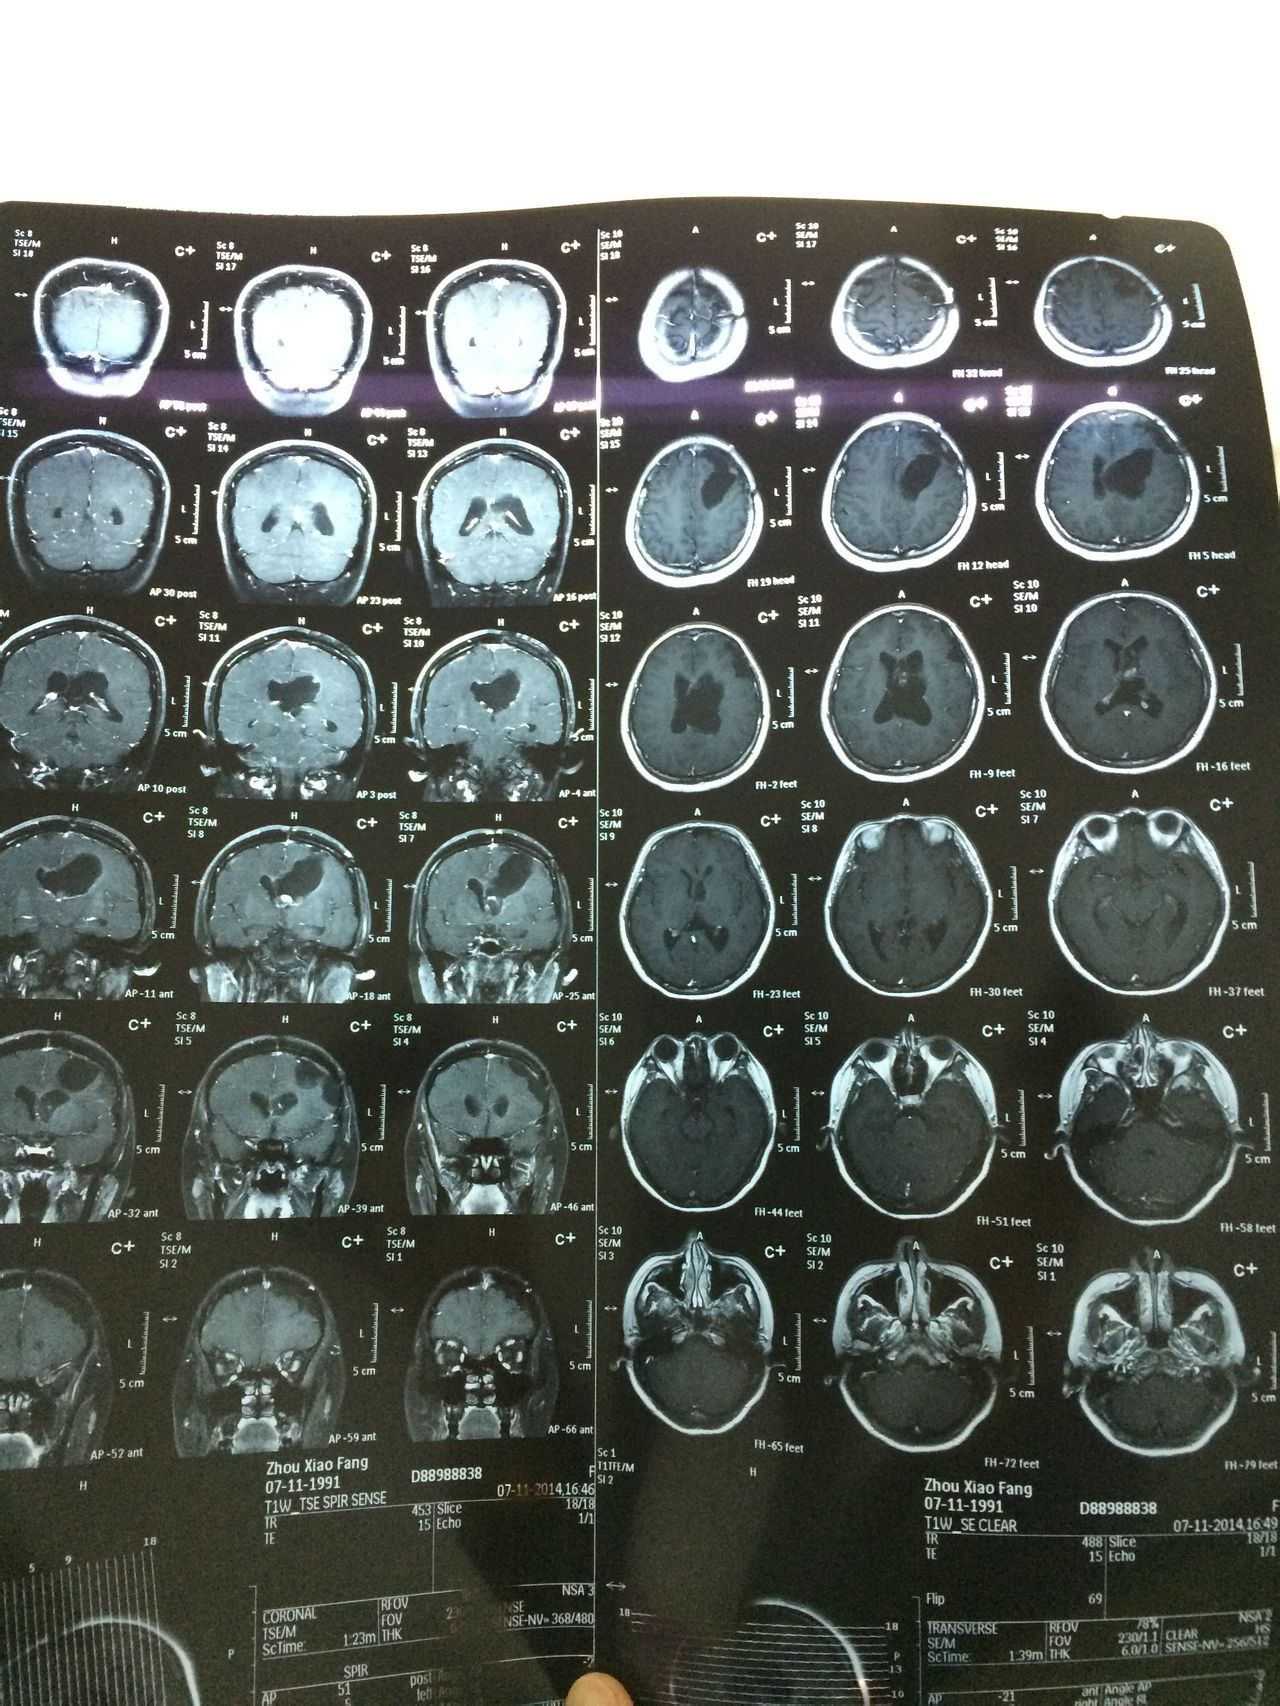

患者女,23岁。2011年9月脑胶质母细胞瘤外科手术,术后无措施,半年复查核磁共振。2013年5月做伽马刀治疗。持续每半年复查核磁共振。    患者身体状况良好,生活上基本没有问题。偶尔出现头晕不排除感冒等因素,但是如果晃到脑部,会有头晕或疼痛感出现。    另外,患者在手术前,经期不规则,大体上一两个月一次,时间不确定。术后,经期不规则更严重,2-3月一次,时间也不固定,但是量少,时有淤血,做过性激素水平检查及妇科常规,正常。2014年11月复查报告麻烦查看附件。    疑问:    1、患者现在需要积极的治疗吗?    2、患者的脑积水严重吗?在这三年内,脑积水虽有波动(增减),但是大体上在一个程度,较稳定。需要做颅内压检查吗?    3、患者现在适合备孕吗?(一直在避孕,暂时未知是否影响怀孕。)这个问题比较复查,还希望各位专家能给予分析利弊。(谢谢!)    3.1、怀孕各个阶段对患者的肿瘤是促进还是抑制作用是否有临床经验供参考?是否可以做一下评估。    3.2、怀孕各个阶段是否会患者造成负担,使其脑积水等加重?    3.3、如果现期不适合备孕的话,有存在“等待”的必要?也或许以后也是这种情况?    最后,很感谢各位专家百忙之中能够为本人了解这份信息。本人是患者的丈夫,发这个问题上来,只是想了解一下情况。虽然我们都很希望能够有爱的结晶,但是我十万分不愿意我的爱人去冒险。各位专家,希望能给予详细的说明和建议。    衷心的祝福你们。

根据影像可以看到脑室轻度扩大,脑胶导劣报质母细胞瘤恶性程度非常高,且术后复发率很高,乔实再加上已经做了伽马刀,对垂体功能影响无法判断。目前治疗口服替莫唑胺治疗,是否可以怀孕,还们院是建议咨询产科医师,详细的检测体内激素水平。